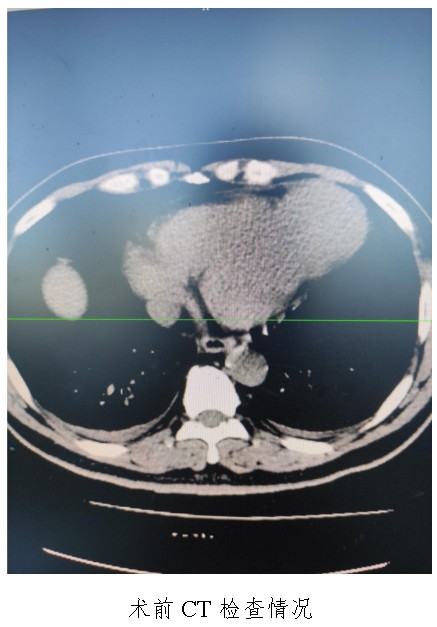

10月18日�,50歲的孟先生因反復(fù)胸悶氣促一周,夜間不能平臥來(lái)衡陽(yáng)市中心醫(yī)院心胸外科就診����,經(jīng)心臟超聲檢查提示左心室前壁中下段及心尖部巨大室壁瘤,66×57mm����,最薄處約3mm?���;颊哂卸嗄晏悄虿〔∈?,既往有無(wú)癥狀心肌梗死病史,曾行PCI治療�����。入科后,廖金文主任�����、屈云劍副主任組織心內(nèi)����、麻醉、體外循環(huán)��、重癥醫(yī)學(xué)科對(duì)病人病情進(jìn)行了多學(xué)科討論���,一致認(rèn)為手術(shù)是治療該病例的唯一手段�����。經(jīng)過(guò)充分的術(shù)前準(zhǔn)備�����,10月24日����,心臟外科團(tuán)隊(duì)給患者實(shí)施了左心室室壁瘤切除加左心室修補(bǔ)成型手術(shù),手術(shù)順利��,術(shù)后經(jīng)過(guò)精心的治療管理��,患者恢復(fù)良好�,康復(fù)出院。該病例的手術(shù)成功��,不僅是術(shù)中及手術(shù)團(tuán)隊(duì)智慧的結(jié)晶���,也是多學(xué)科合作的結(jié)果����,展示了衡陽(yáng)市中心醫(yī)院處理復(fù)雜危重患者的能力�����。